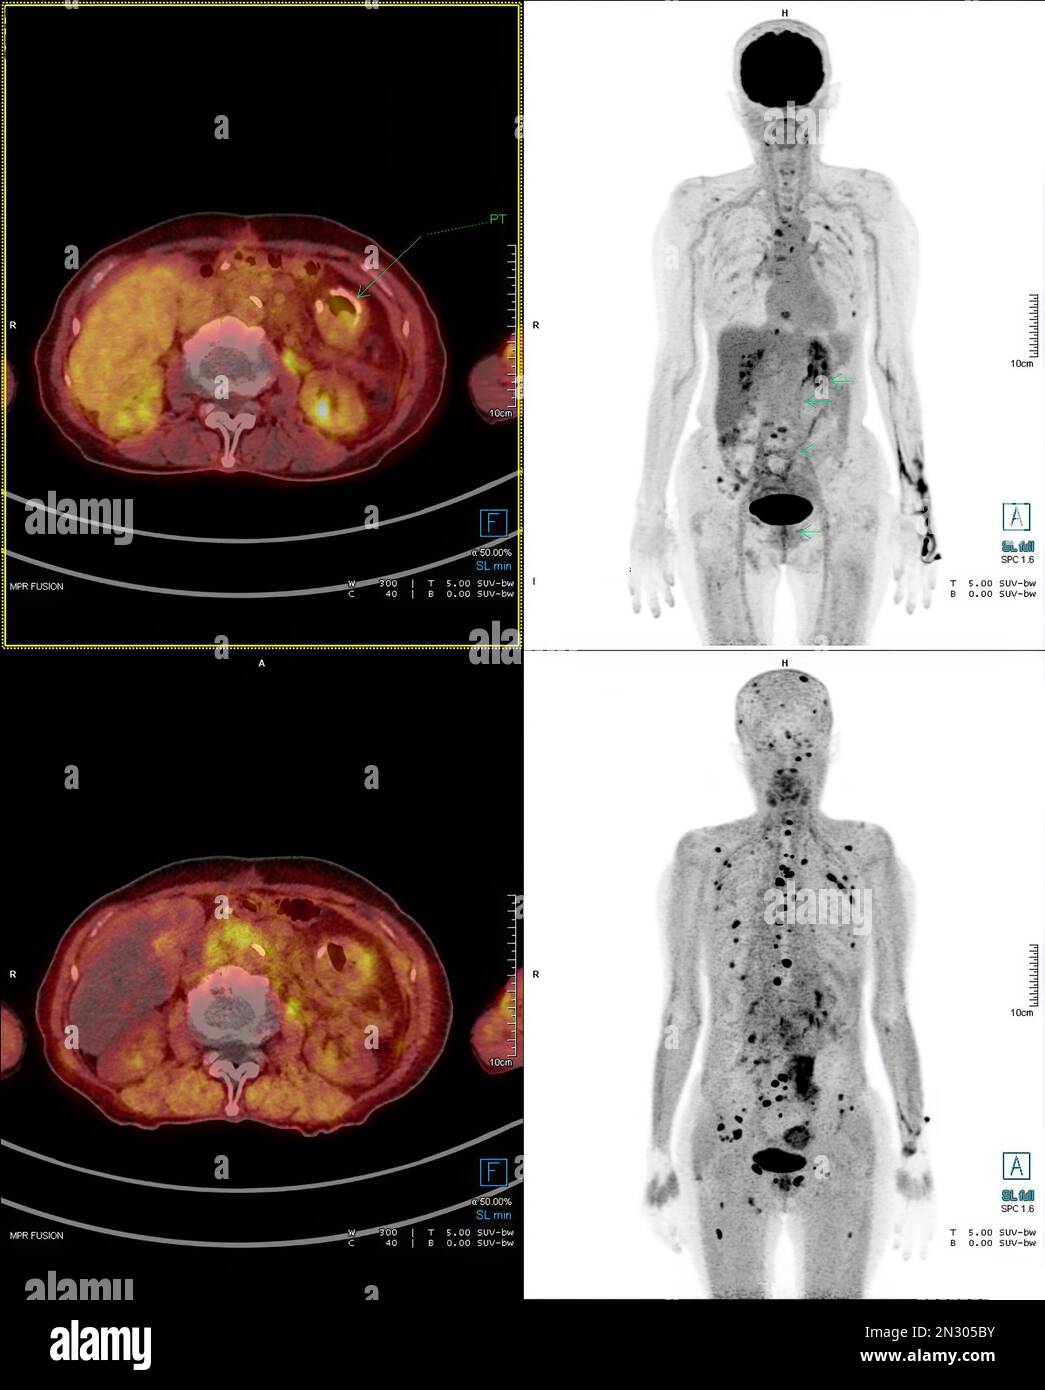

RF2N305BY–La tomographie par émission de positrons (TEP) CT scan utilise un médicament radioactif (traceur) pour montrer l'activité métabolique normale et anormale de tout le corps humain

RF2N305M5–La tomographie par émission de positrons (TEP) CT scan utilise un médicament radioactif (traceur) pour montrer l'activité métabolique normale et anormale de tout le corps humain